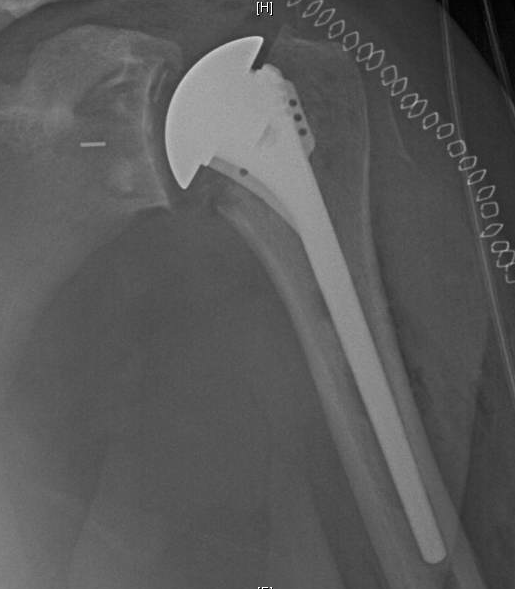

Here is the x-ray of a middle aged lady with glenohumeral arthritis.

She had a total shoulder arthroplasty at which time her rotator cuff was reported to be normal. A large diameter humeral stem was used that was incompletely seated in the humeral canal because of diaphyseal incarceration, leaving the humeral head high above the tuberosity.

Three months after surgery she presented to us for consultation regarding weakness and pain. On examination she had pseudoparalysis and these x-rays.

Comment: The point here is that a stem that fits tightly in the diaphysis may be difficult to seat completely. A high humeral head can put the rotator cuff at risk and lead to cuff failure and pseudoparalysis.